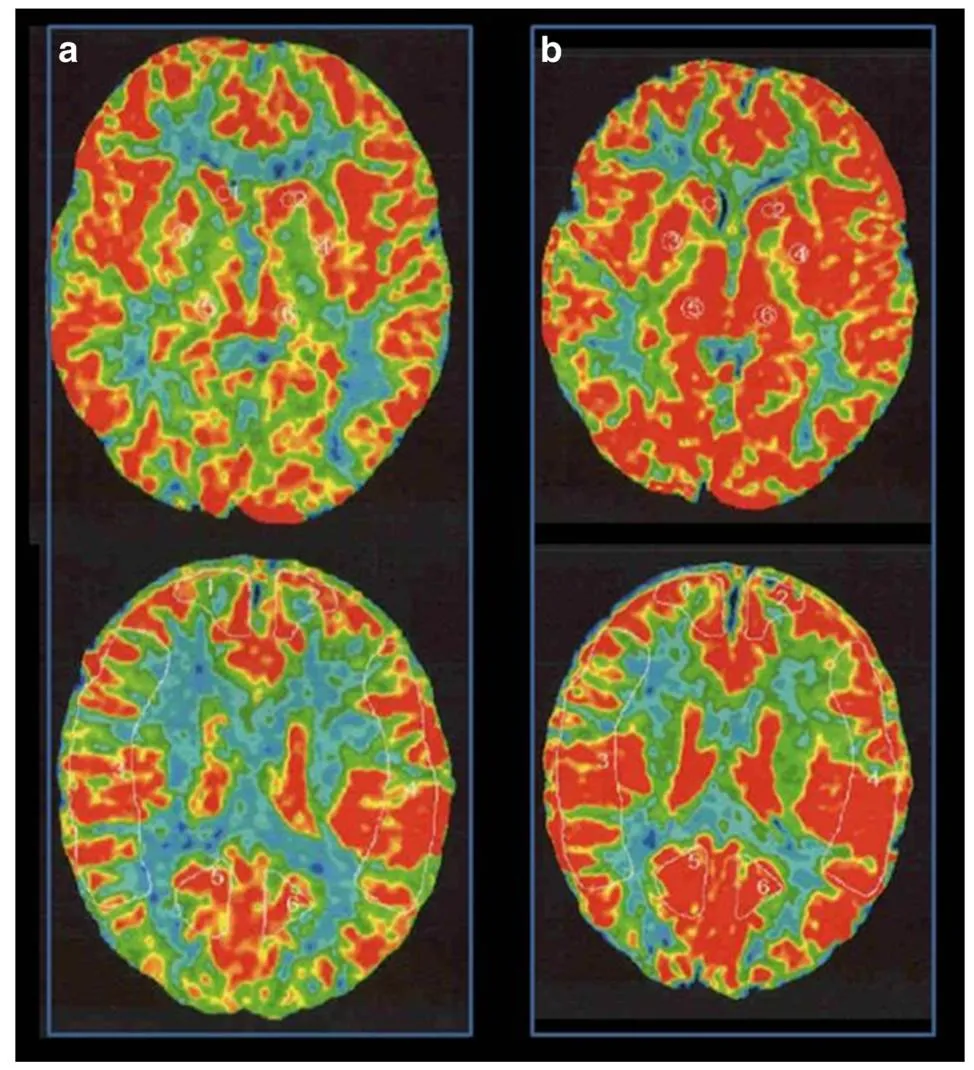

脑血流检查(XeCT,氙气计算机断层扫描):静息状态下脑血流量基本正常,药物负荷后脑血管反应性轻度下降,但未出现明显缺血区域。(图2)

图2术前脑血流检查显示静息状态下双侧脑血流无显著差异(a),乙酰唑胺注射后右侧大脑中动脉供血区脑血管反应率为14.8%(b)